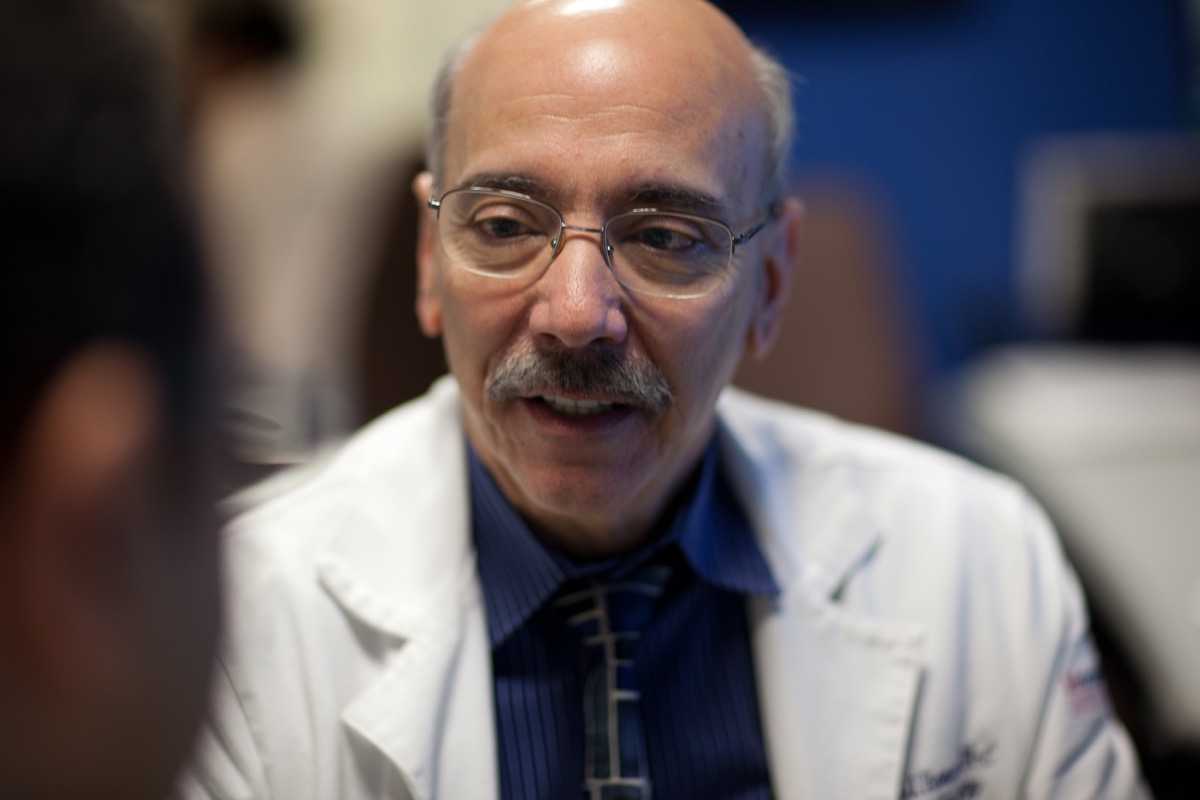

Judah Burns, MD, Director, Diagnostic Radiology Residency Program, Vice Chair of Education, and Jacob Cynamon, MD, Director, Integrated Interventional Radiology Program

Faculty and scientists at the forefront of research

A world-renowned faculty

Jacqueline A. Bello, MD, FACR, Director, Neuroradiology